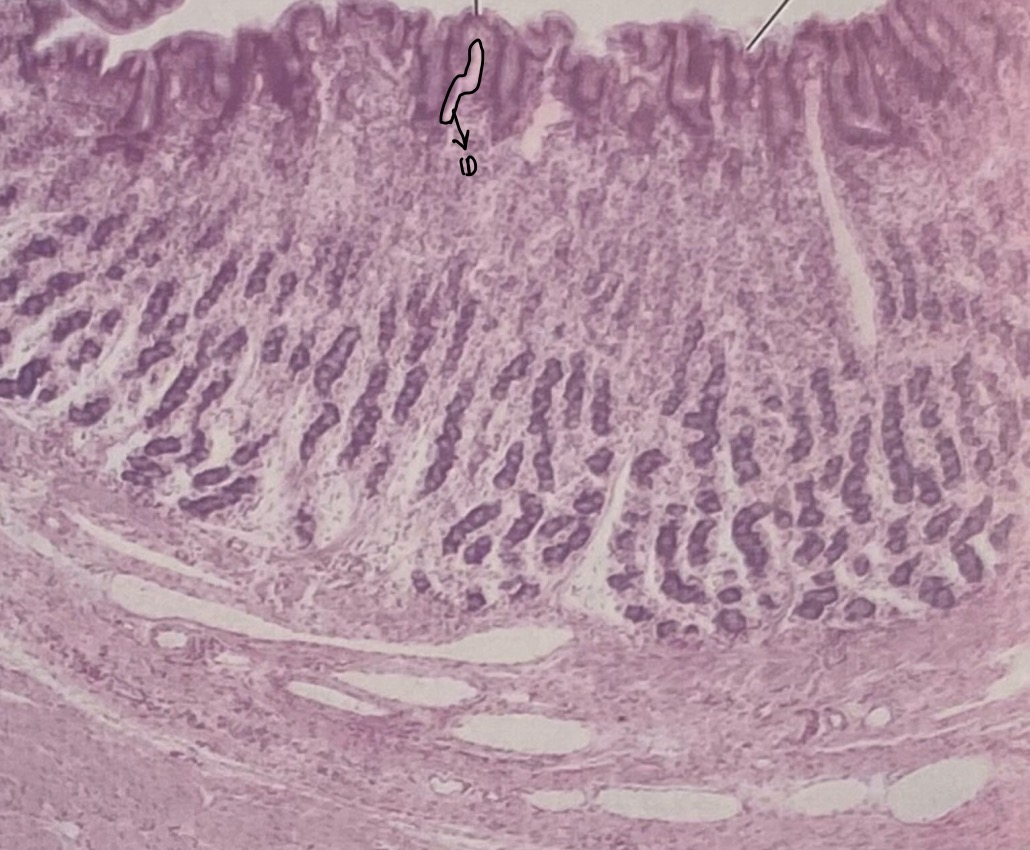

Stomach

Gastric Pit

Mucosal Cells

Parietal Cells

Chief Cells